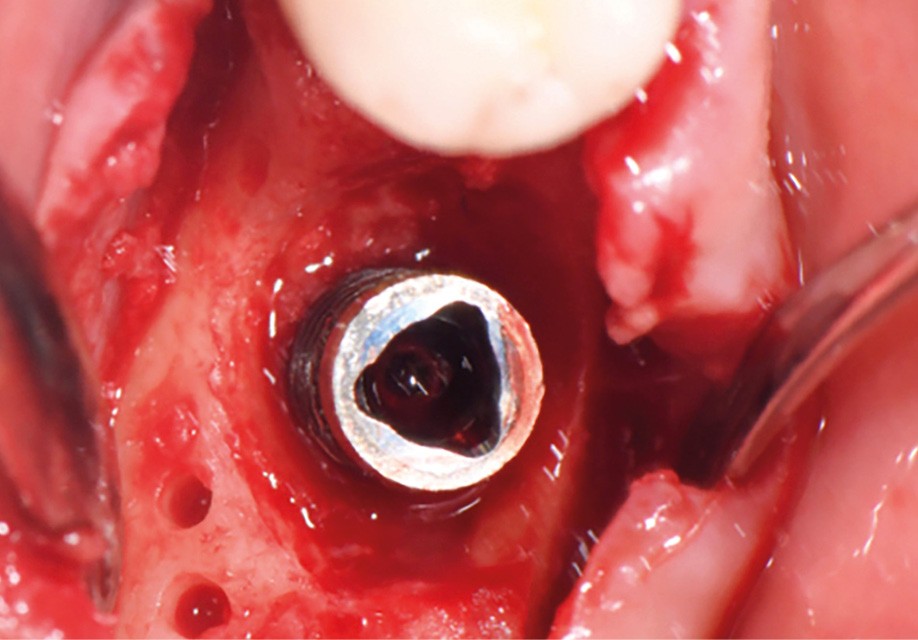

Actes préopératoires